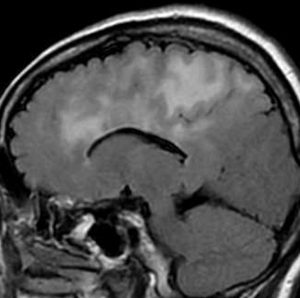

左側頭葉のびまん性星細胞腫です。左側のT1強調ガドリニウム像ではほとんど腫瘍は見えません。真ん中のT2強調画像でも見づらいです。右側のフレア画像で白くにじんでいるところに腫瘍があります。どこまでが腫瘍の境界なのかがはっきりしない腫瘍です。左の海馬(記憶の中枢)を侵し,とてもゆっくり大きくなるタイプで,この患者さんは10年以上治療をしないで経過を見ています。全摘出できない星細胞腫グレード2です。